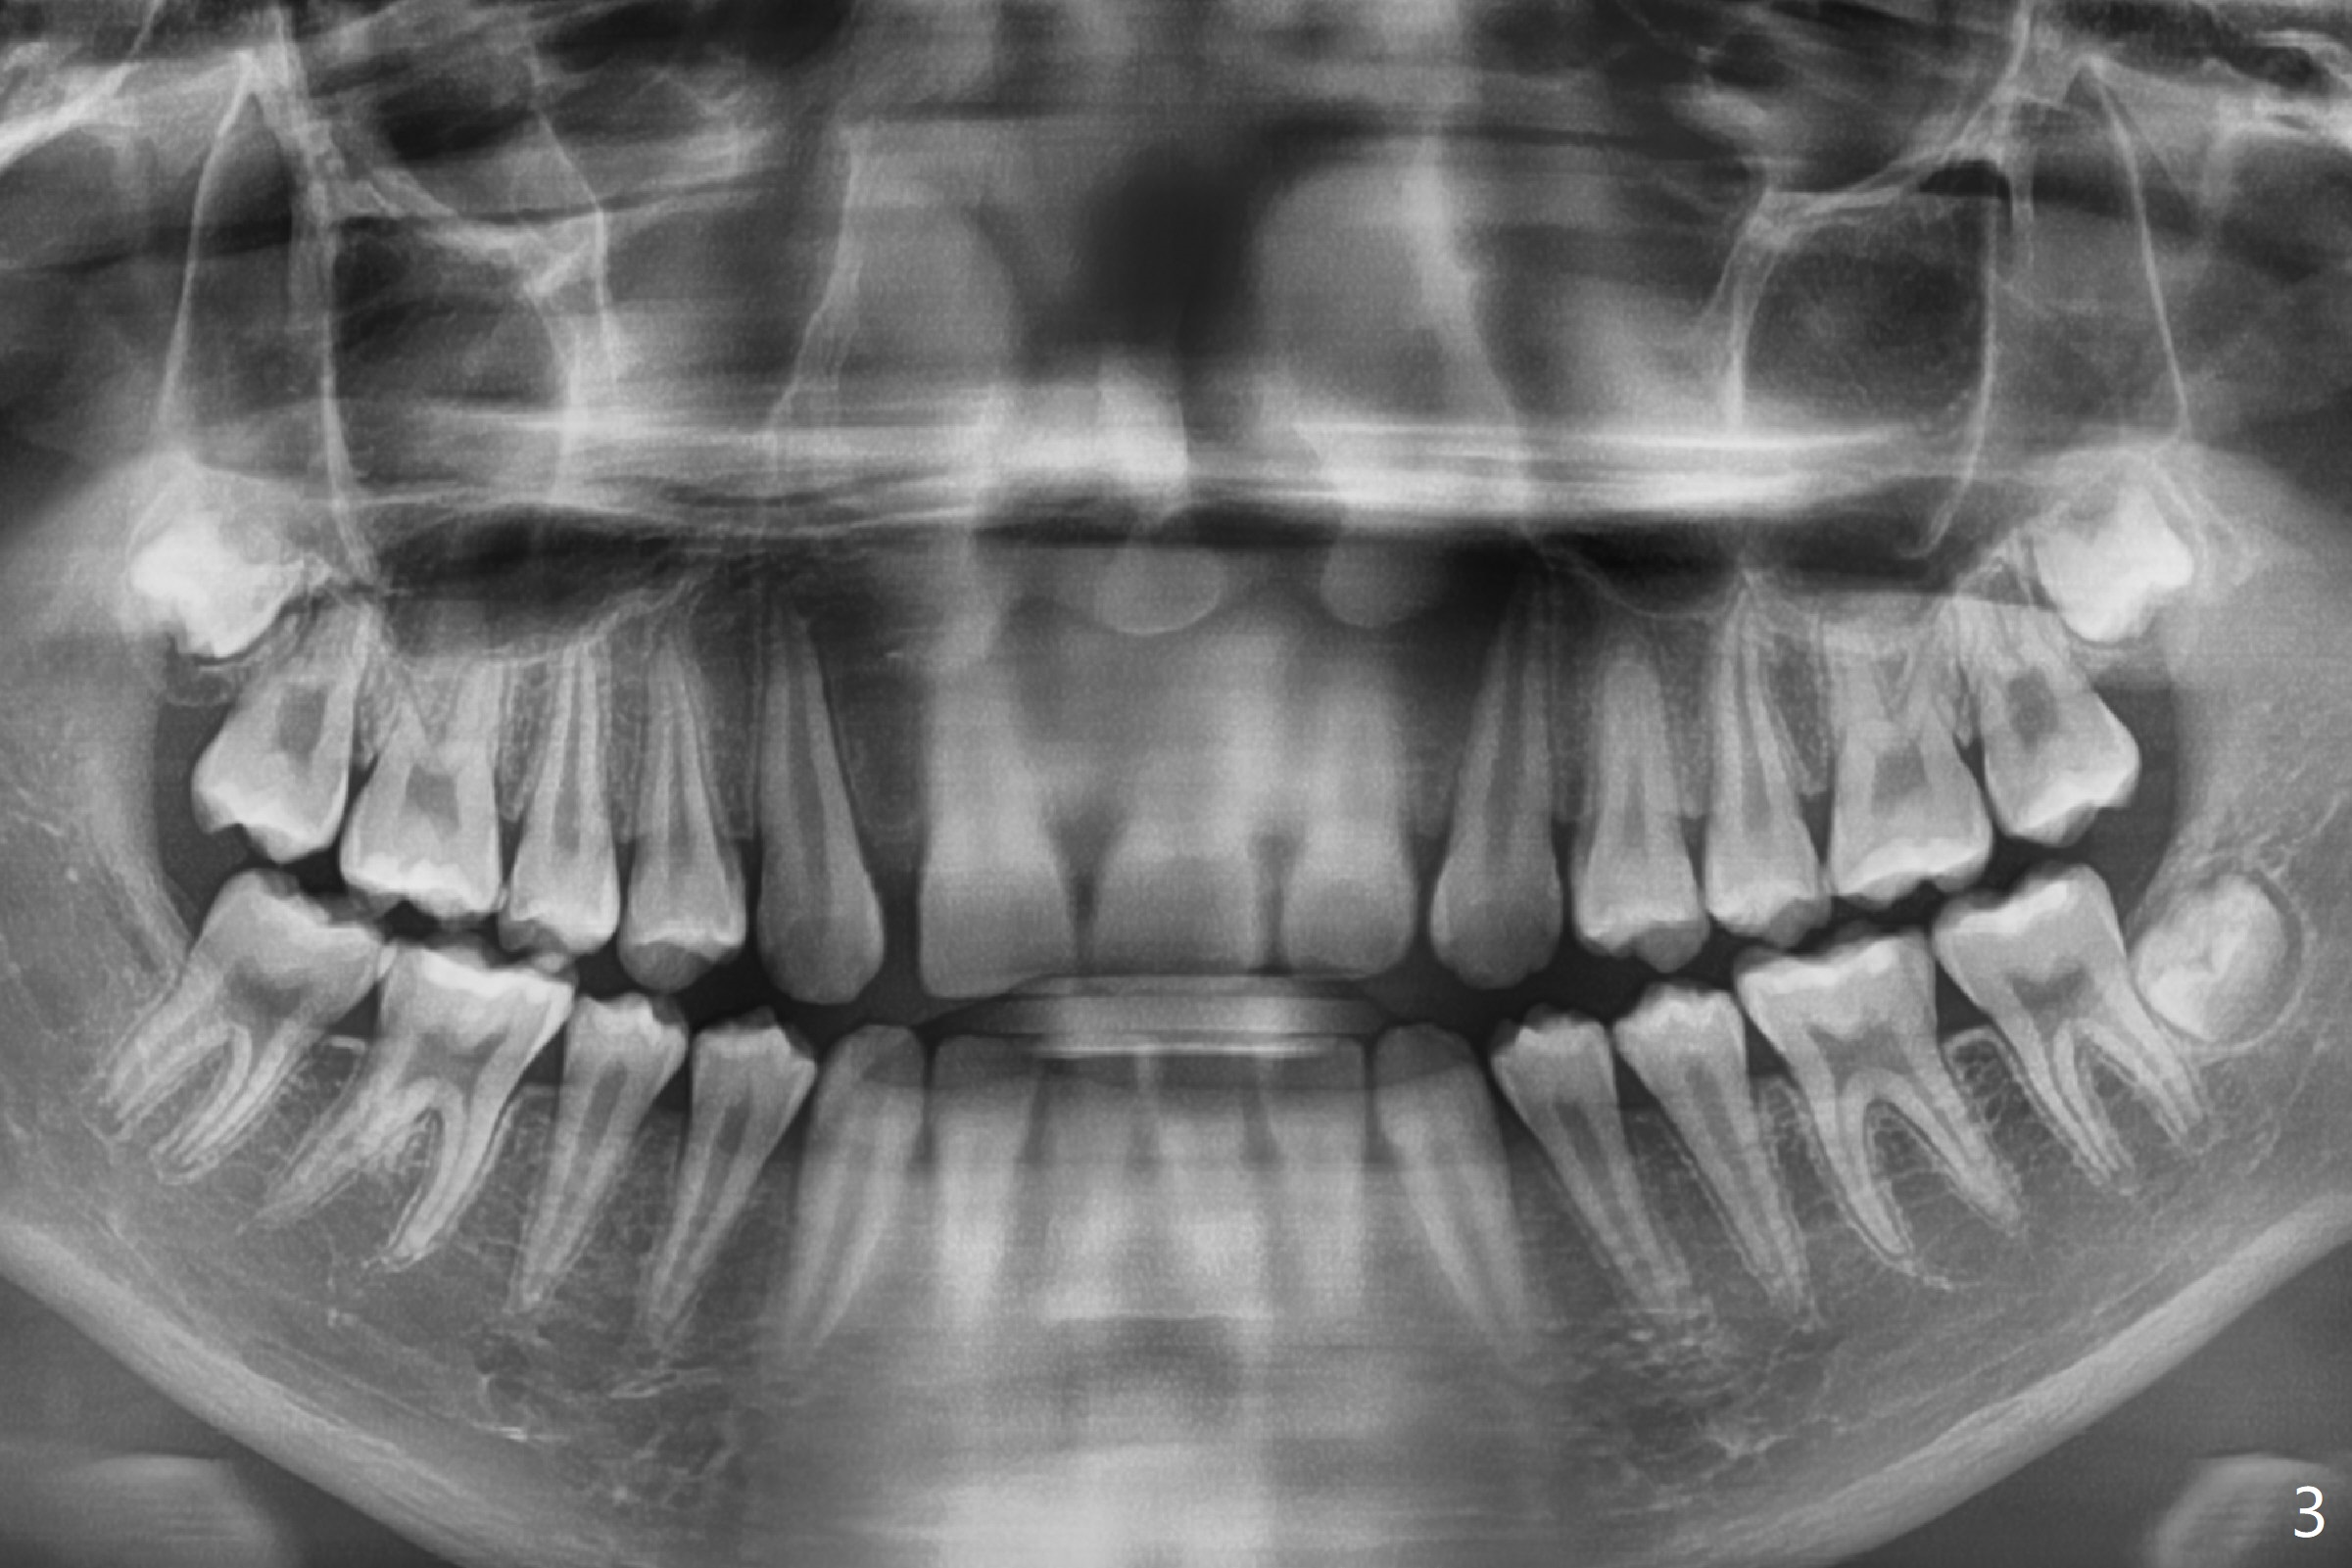

A 14-year-old man requests ortho because of crowding lower anterior and UR missing lateral (Fig.1-4). Open space for the future implant at UR2 will correct upper midline deviation (Fig.1) and change Class II malocclusion to I on the right (Fig.6, as compared to Fig.7). To control UR1,3 root torque, bracketing on these 2 teeth will be intentionally off (Fig.5). The treatment will take ~ 2 years. Prior to implantation at UR2, what type of prosthesis should be made?